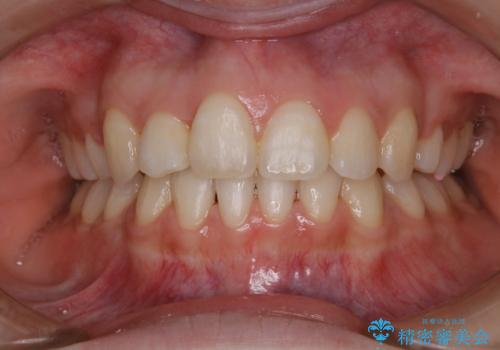

ホワイトニング 1日で真っ白な歯に

- ホワイトニングで歯を白くしたいとのことでした。

処置前クリーニング¥3300・オフィスホワイトニングのエクセレントコース¥29700を行いました。

- ¥33000費用は治療当時の料金となります